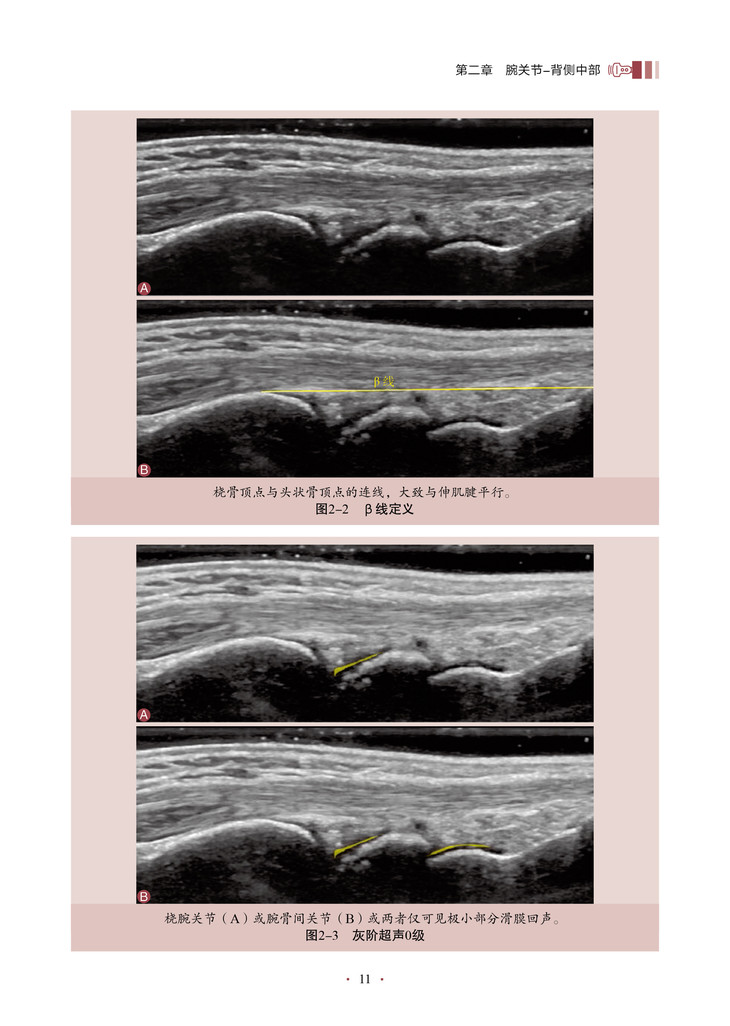

本书的核心内容是将超声技术应用于关节炎程度的评估,特别是对关节滑膜炎症的评分和客观量化。通过详细地介绍超声评分系统的构建和应用,作者为我们展示了一种全新的、基于客观指标的关节炎评估方法。该书深入探讨了关节滑膜超声图像的解读和分析,教导读者如何识别和评估关节炎引起的滑膜病变。通过使用可靠的超声评分系统,医师和研究人员能够更准确地量化关节炎患者的炎症程度和疾病进展,从而更好地指导治疗和监测疗效。